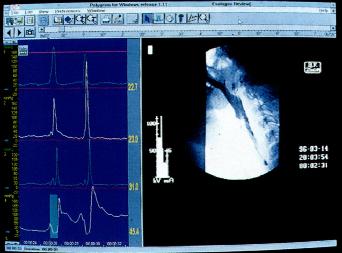

同步吞钡透视及测压检查(图2.5)

为评价吞咽异常可同步进行咽部测压及X线透视。钡透视显影与生理指标记录同步进行,检测同步显示,并以数字方式记录在同一计算机上。

图2.5 同步钡透及测压检查(图取自Medtronic GastroIntestinal).